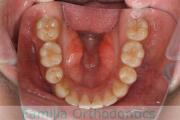

- ≫治療前

上顎

下顎

- ≫治療中 ステップ1